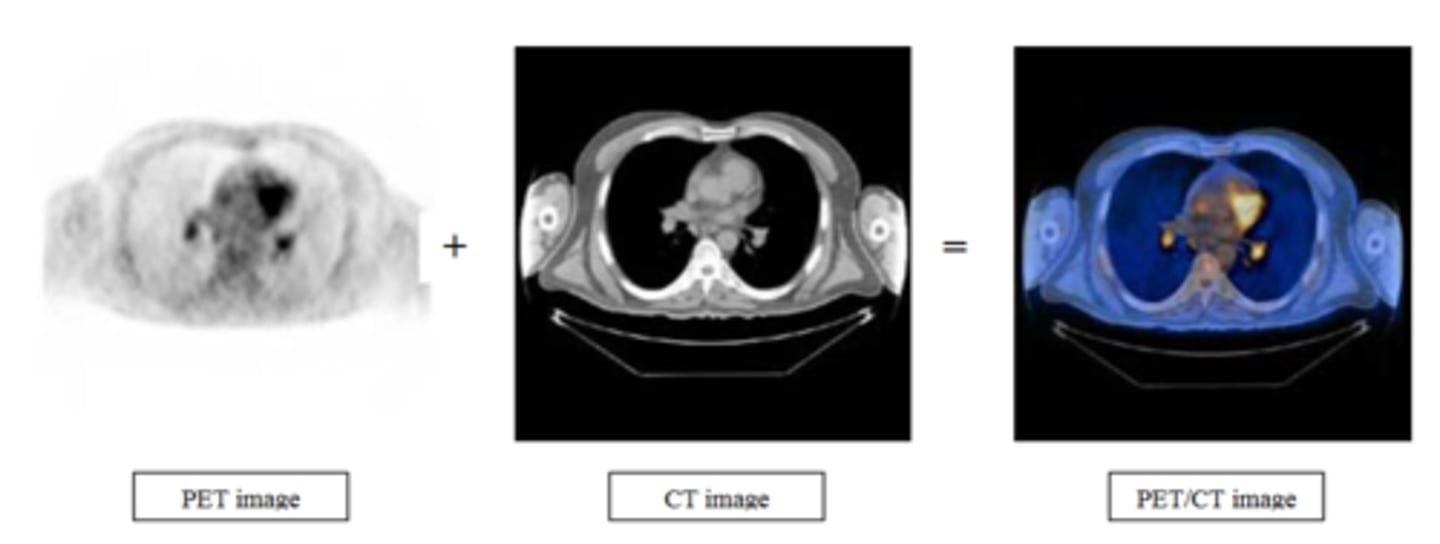

What does PET stand for in medical imaging?

Positron Emission Tomography

How does the combination of CT and PET imaging benefit medical imaging?

Combines CT's anatomic detail and PET's physiologic detail for high quality images